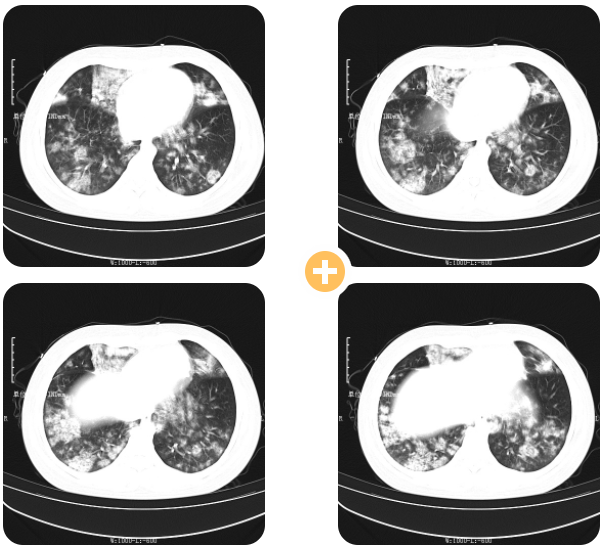

刚入院时胸部CT结果显示如下:

检查结果回示,小毛肺部病灶弥漫,双肺见多发片状磨毛玻璃影,呈现“白肺”表现,小毛感染非常重,新型冠状病毒核酸阳性,呼吸道多种病原体靶向测序报告结果显示:鲍曼不动杆菌感染,感染较重立即下病危通知。